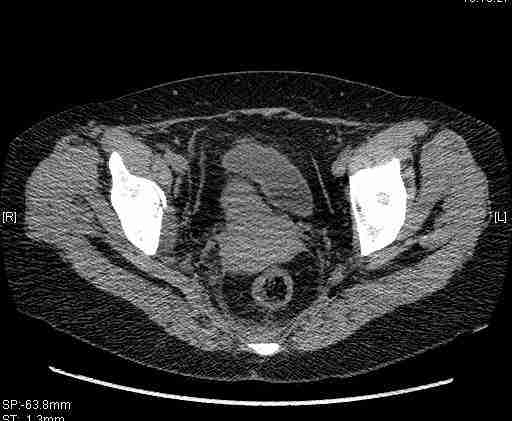

Удалось сегодня вывести пациентку в соседнюю больницу, где есть кт. Срезы сделаны только горизонтальные.